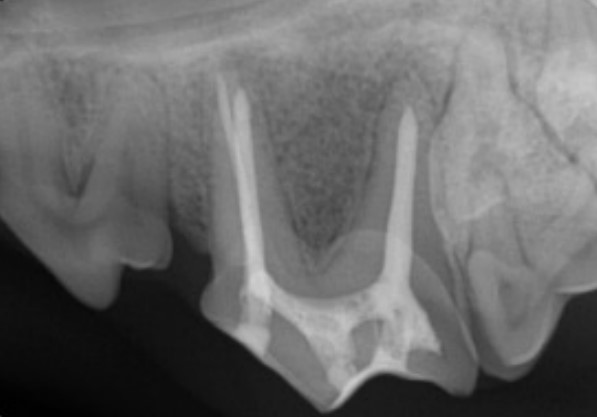

Figure 1: Fourth premolar tooth after root canal treatment

Root canal treatment on teeth with older fractures or on non-vital teeth can also be performed. The infected pulp and a thin layer of dentin lining the pulp canal is removed from the tooth using endodontic files. The pulp canal is flushed with disinfectant and the tooth is filled with an inert sealant called gutta percha. The fracture site and site used to access the pulp canal are filled with composite.